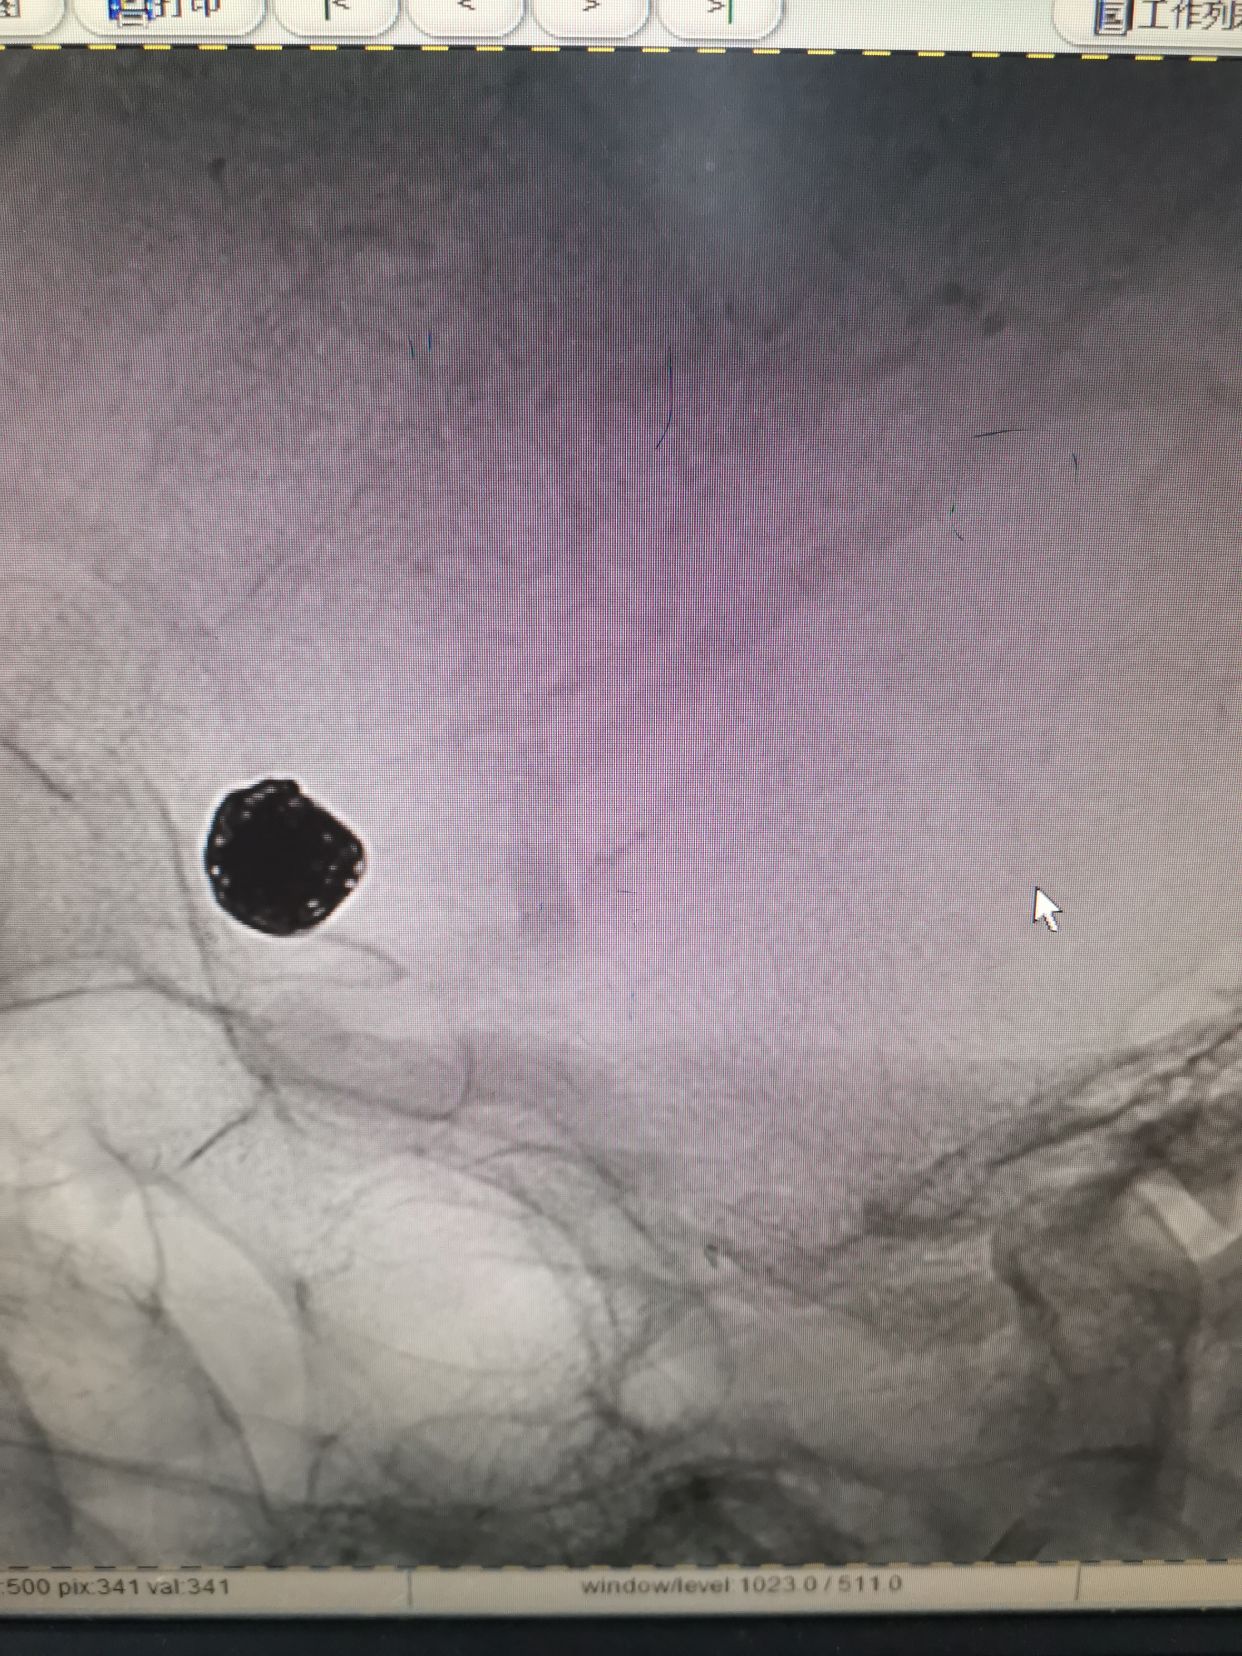

左侧颈内动脉3D